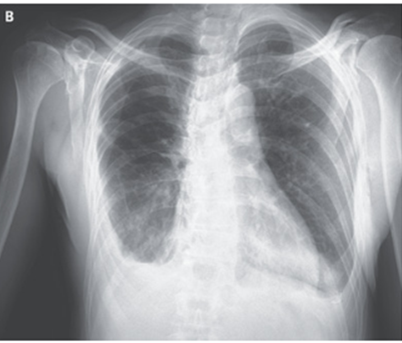

僧帽弁逆流に伴う心不全と診断し、利尿薬と血管拡張薬投与がなされた。3日後のX-p所見。

右肺のレンズ状病変は完全に消失し、肺水腫が減少していることが示唆された。

右肺のレンズ状病変は局在性の葉間胸水と考えられた。

HFrEF改善後、循環器内科で冠動脈評価が行われ、3枝病変が存在することが分かり、外科的冠動脈血行再建術および僧帽弁置換術が施行された。術後1か月後時点では患者の状態は良好である。